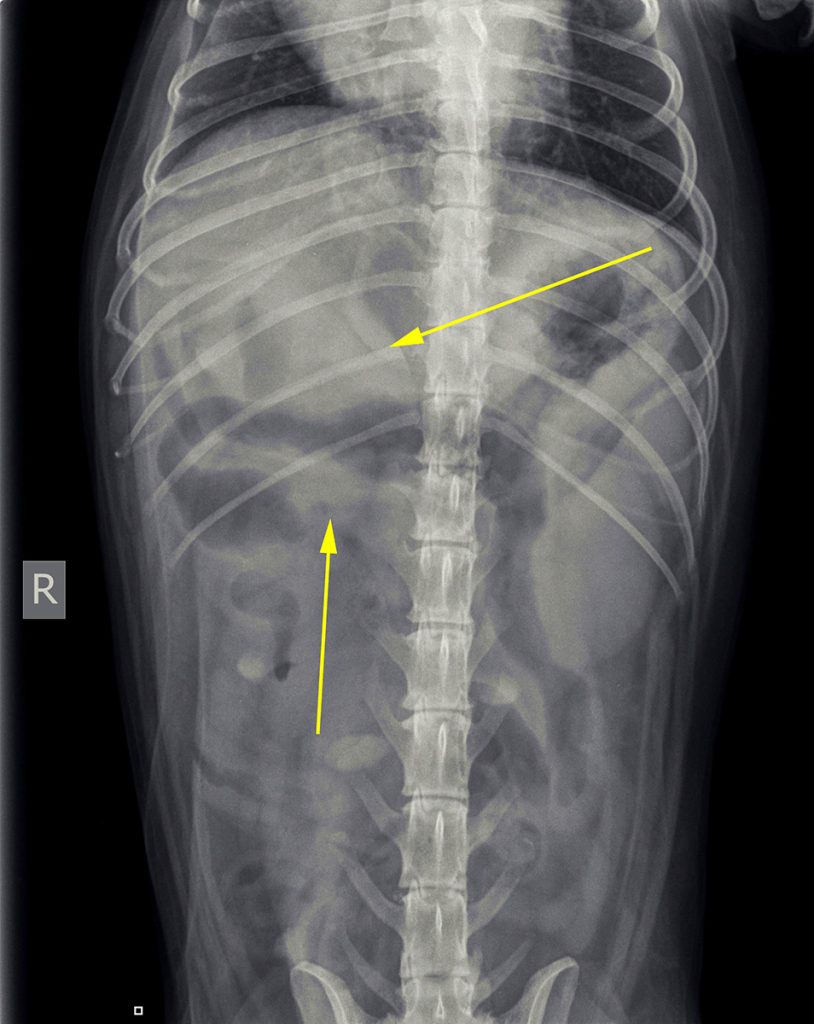

Op basis van deze afwijkingen is er toen voor gekozen om röntgenfoto’s te maken.

De belangrijkste afwijkingen die op de röntgenfoto’s te zien waren: minder contrast dan we gebruikelijk zien en mogelijk een structuur. Er was echter geen aanwijzing voor een verstopping.